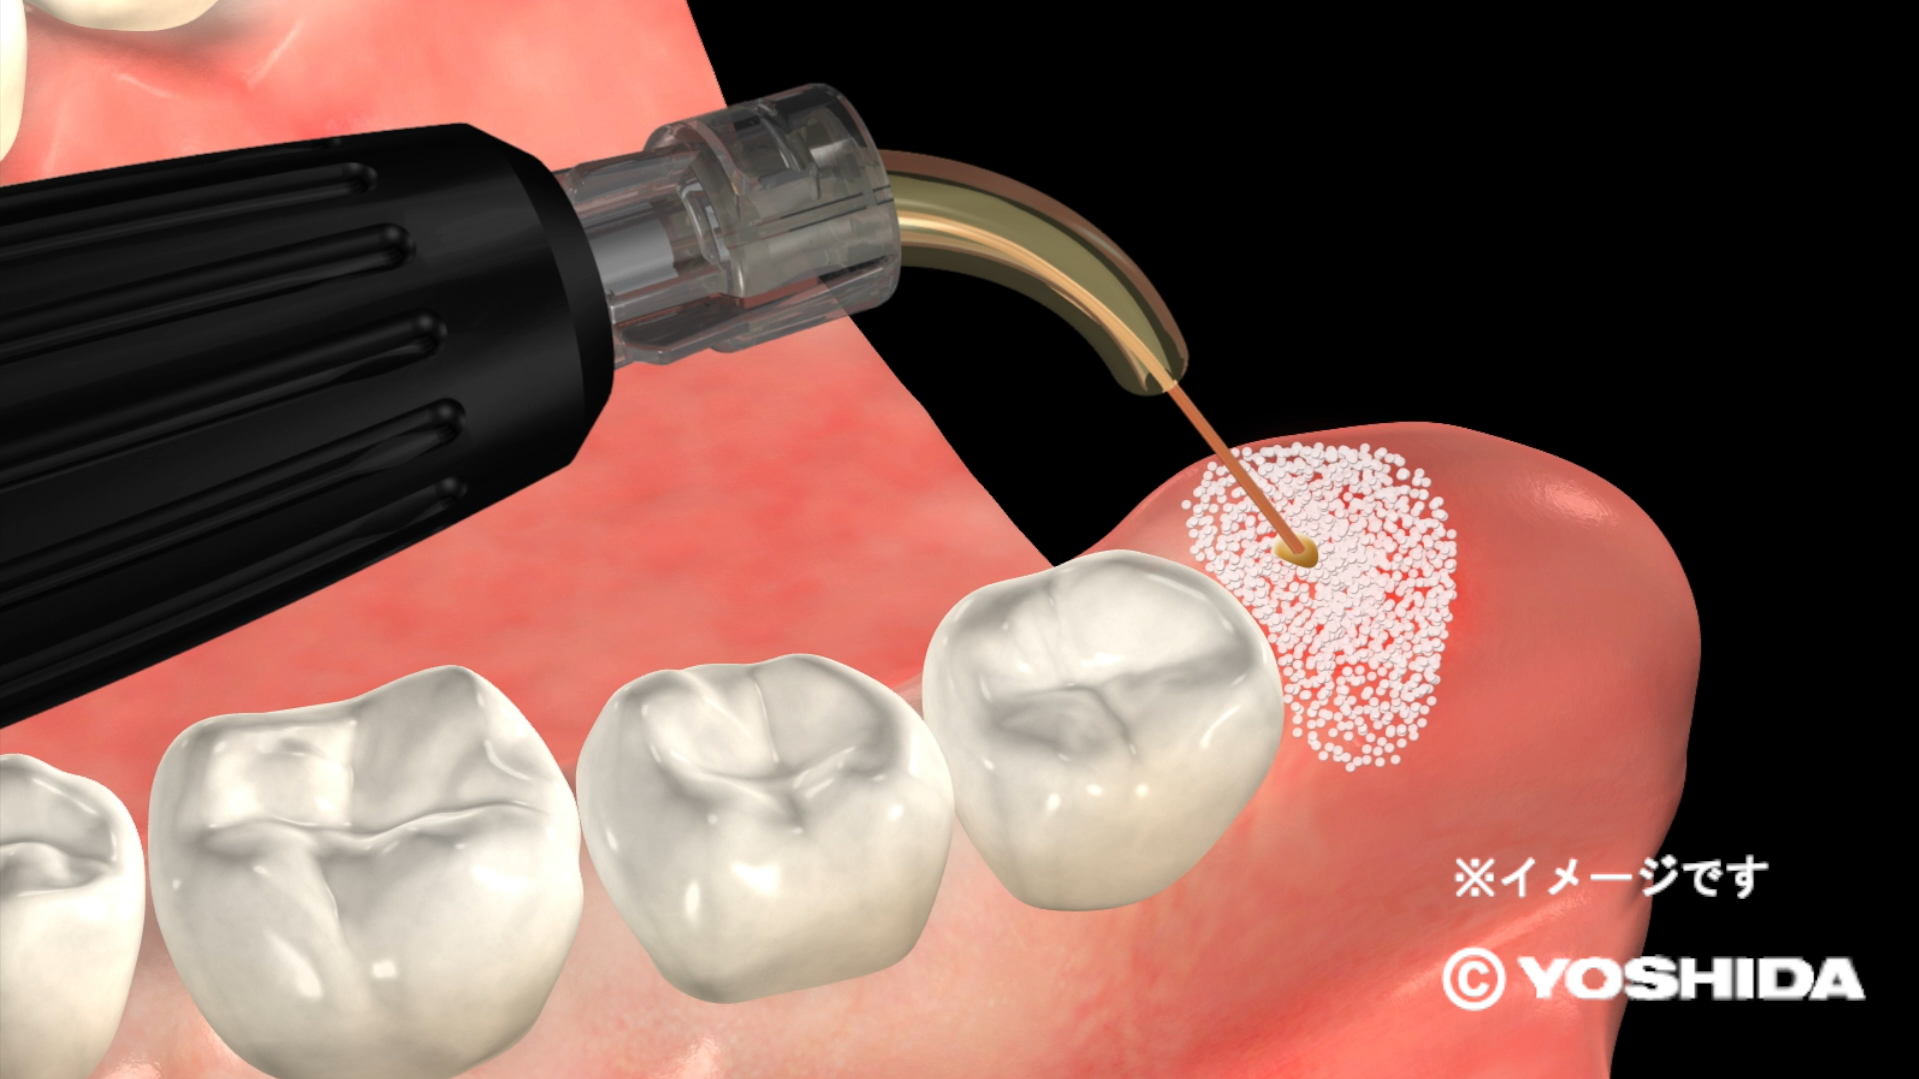

(1)オペレーザー商品とは、株式会社吉田製作所が製造する歯科用レーザー機器であって、「オペレーザー」を販売名に含む商品をいいます。